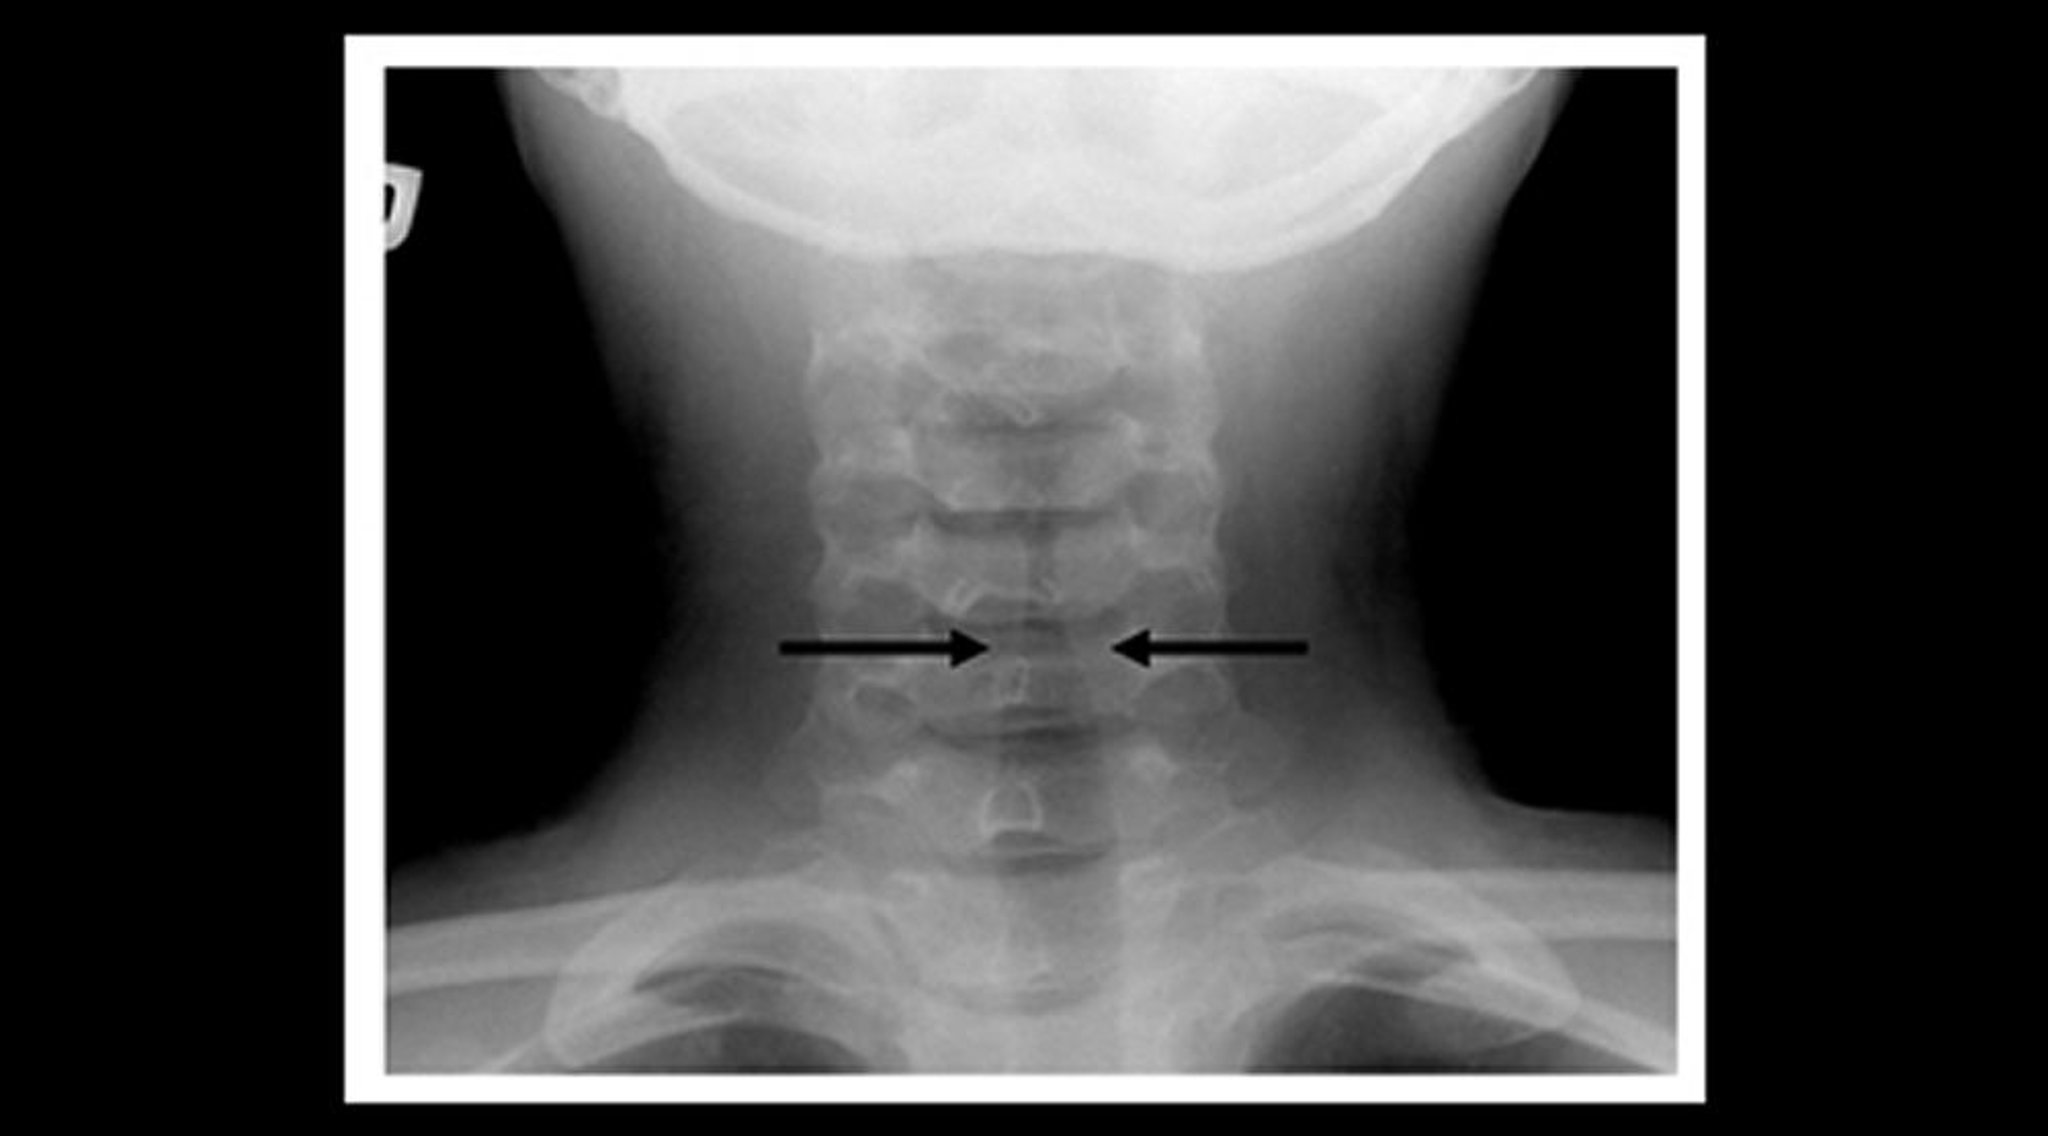

Röntgenbild eines Kindes mit Krupp (koronale Ansicht)

Röntgenaufnahmen der Halsweichteile eines Kindes mit Krupp zeigen eine allmähliche Einengung des subglottischen trachealen Luftschattens (Kirchturm-Zeichen; Pfeile) und eine Erweiterung der pharyngealen Luftzwischenräume.

Image courtesy of John McBride, MD.